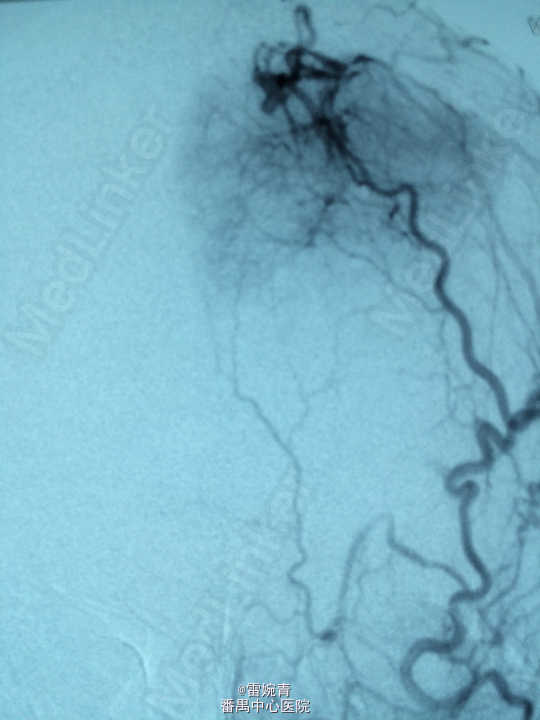

诊断:脑膜瘤 处理:先行DSA检查以明确脑膜瘤的供血动脉情况,见:肿瘤染色,肿瘤主要由左侧眼动脉供血,用Glubran胶将其闭塞,后择期行手术切除治疗。术后病理证实为脑膜瘤。

术后患者病情稳定,后出院。 讨论:脑膜瘤可由颈内颈外动脉双重动脉供血,血供较为丰富,直接开颅手术治疗出血量较多,如果能术前行介入栓塞治疗可减少书中出血量,并降低手术风险及难度。